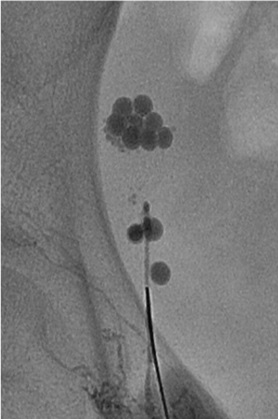

Intranodal lymphangiography by injecting Lipiodol through a 25-gauge needle

Injection of N-butyl cyanoacrylate (NBCA)

1:1 dilution with Lipiodol

Dose: 0.5 – 1.0 mL/puncture